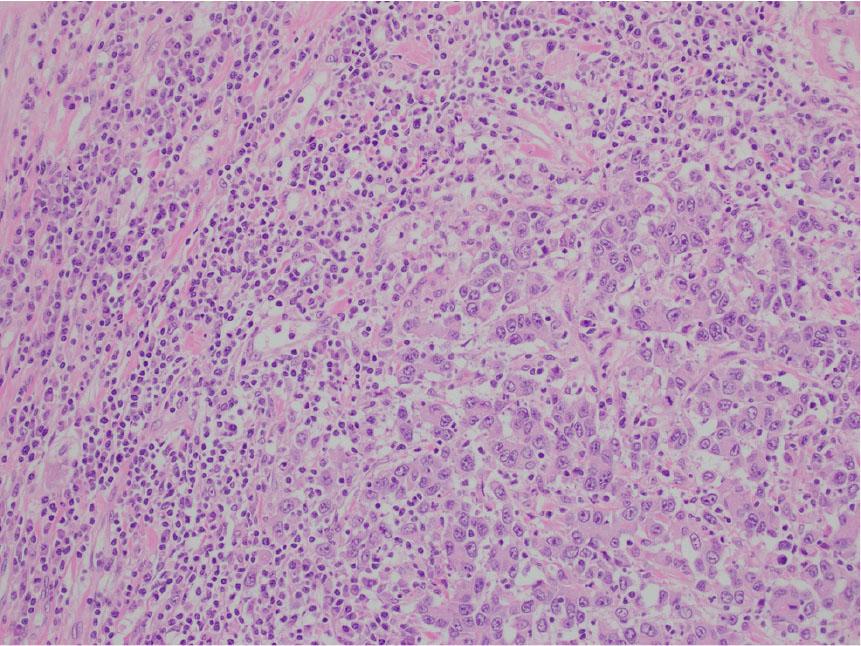

Higher magnification reveals poorly differentiated cells with medium to large-sized vesicular nuclei, nucleoli, and moderate eosinophilic cytoplasm. The larger carcinomatous cells are interspersed by the smaller tumor infiltrating lymphocytes.

The medullary carcinoma is composed of poorly to undifferentiated cells in a vaguely trabecular to solid pattern. It lacks the typical glandular formation and mucin content seen in traditional colonic adenocarcinomas. The carcinoma has a circumscribed, pushing border, with a brisk intraepithelial and peritumoral lymphocytic infiltration.